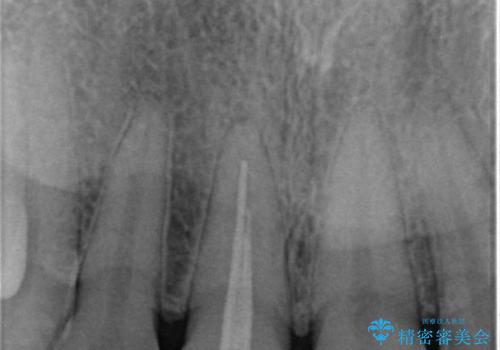

根管治療をした歯は神経のある歯と比較して強度が下がり、長期的に破折のリスクが高まると言われています。破折のリスクを軽減させるため、根管治療を行った歯に対しては歯冠をすべて覆うクラウンという被せ物にて補綴処置を行います。

適合不良の補綴物は二次的な虫歯発生のリスクが高まります。

自費診療で用いられる材料は保険適応の材料に比べて、より精密で適合の良い被せ物作ることができるため、長期的な虫歯のリスクを大幅に減らすことが可能です。